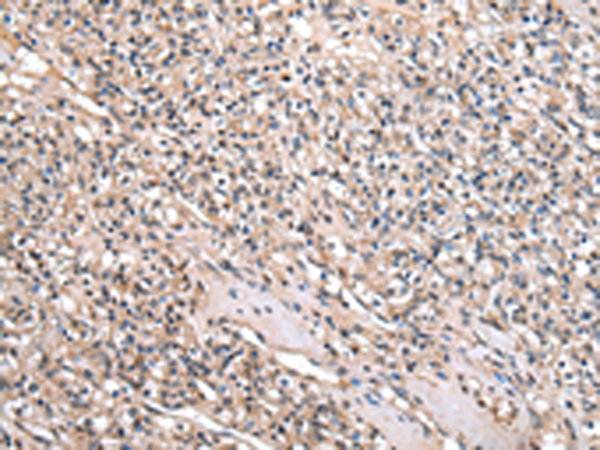

分类: 科研抗体货号: P01968别名: HCG-1; PNSC1应用: IHC反应种属: Human, Mouse, Rat